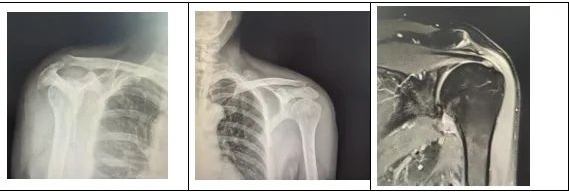

经过团队反复研讨,副主任医师李政为王先生实施了左肩关节松解术,肩袖锚钉缝合术,并在术中使用了双排锚钉。双排锚钉可以提供更强大的稳定性,可以使得肩关节在术后可以进行早期功能锻炼。该手术完美解决了治疗中的矛盾,整个手术过程不过两个小时。